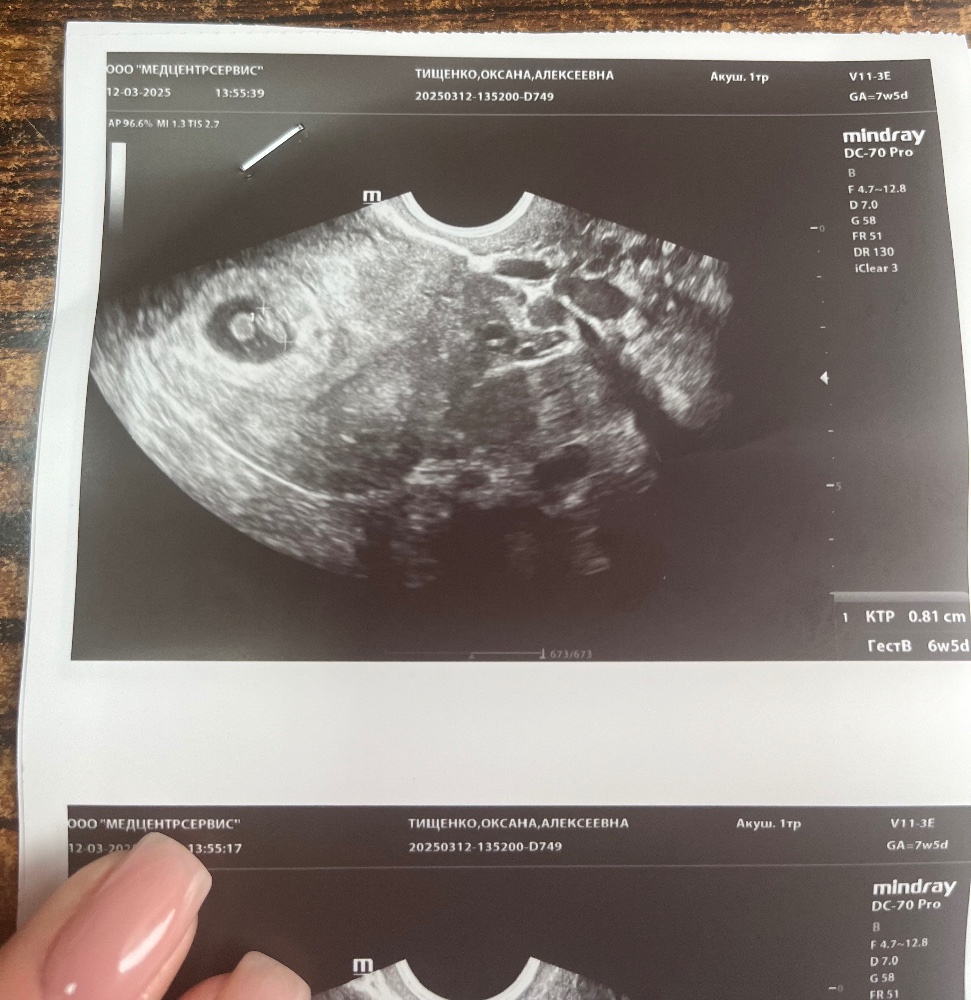

Сегодня сходила на повторное узи в другую клинику после пятничного.

в пятницу ктр был 5, плодное яйцо 9,7. Я начиталась таких ужасов за это время. У 95% всех ситуаций была в итоге замершая при таких показателях. Я уже настроила себя на самое плохое.

И вот сегодня мне выдают, плодное яйцо 21х20х22, эмбрион 8,1мм. ЧСС 152.

Я просто в приятном шоке, как так? Как за 5 дней плодное яйцо увеличилось более чем на 10 мм? Магия. Либо узист в тот раз криво посмотрел 🤷🏻♀️

Криво намеряли,пя если плохо растет,то оно и потом плохо растет,а у вас нормально росло,врятли за 5 дней оно так выросло,у вас сейчас получается свд пя 21,оно растет примерно 1 мм в сутки,значит 5 дней назад было не 9,7,а 16 мм,а у вас точно пя свд 9,7 было или там несколько размеров,как здесь,просто смотрят не какую-то одну сторону,а считают свд,если три значения,то их складывают и делят на 3,если два,то анологично складывают и делят на 2 уже

Марина, да, в прошлый раз сказали свд-9,7 мм. Мерили по 2м сторонам. Каждая из сторон была 9 с чем-то. В общем, не понимаю как так могли намерить.